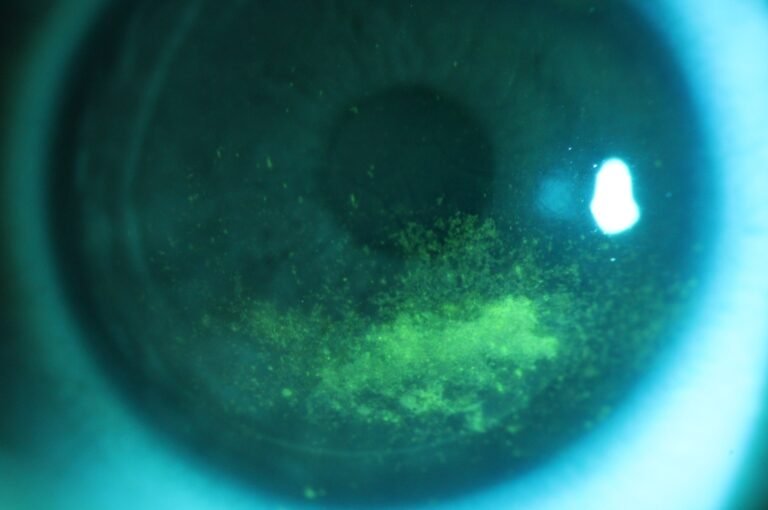

Integrated Filters

Built-in Yellow Filter

The PSL-9000 features a built-in yellow barrier filter that works in combination with cobalt blue illumination to reveal sodium fluorescein staining patterns on the cornea and ocular surface with exceptional clarity.